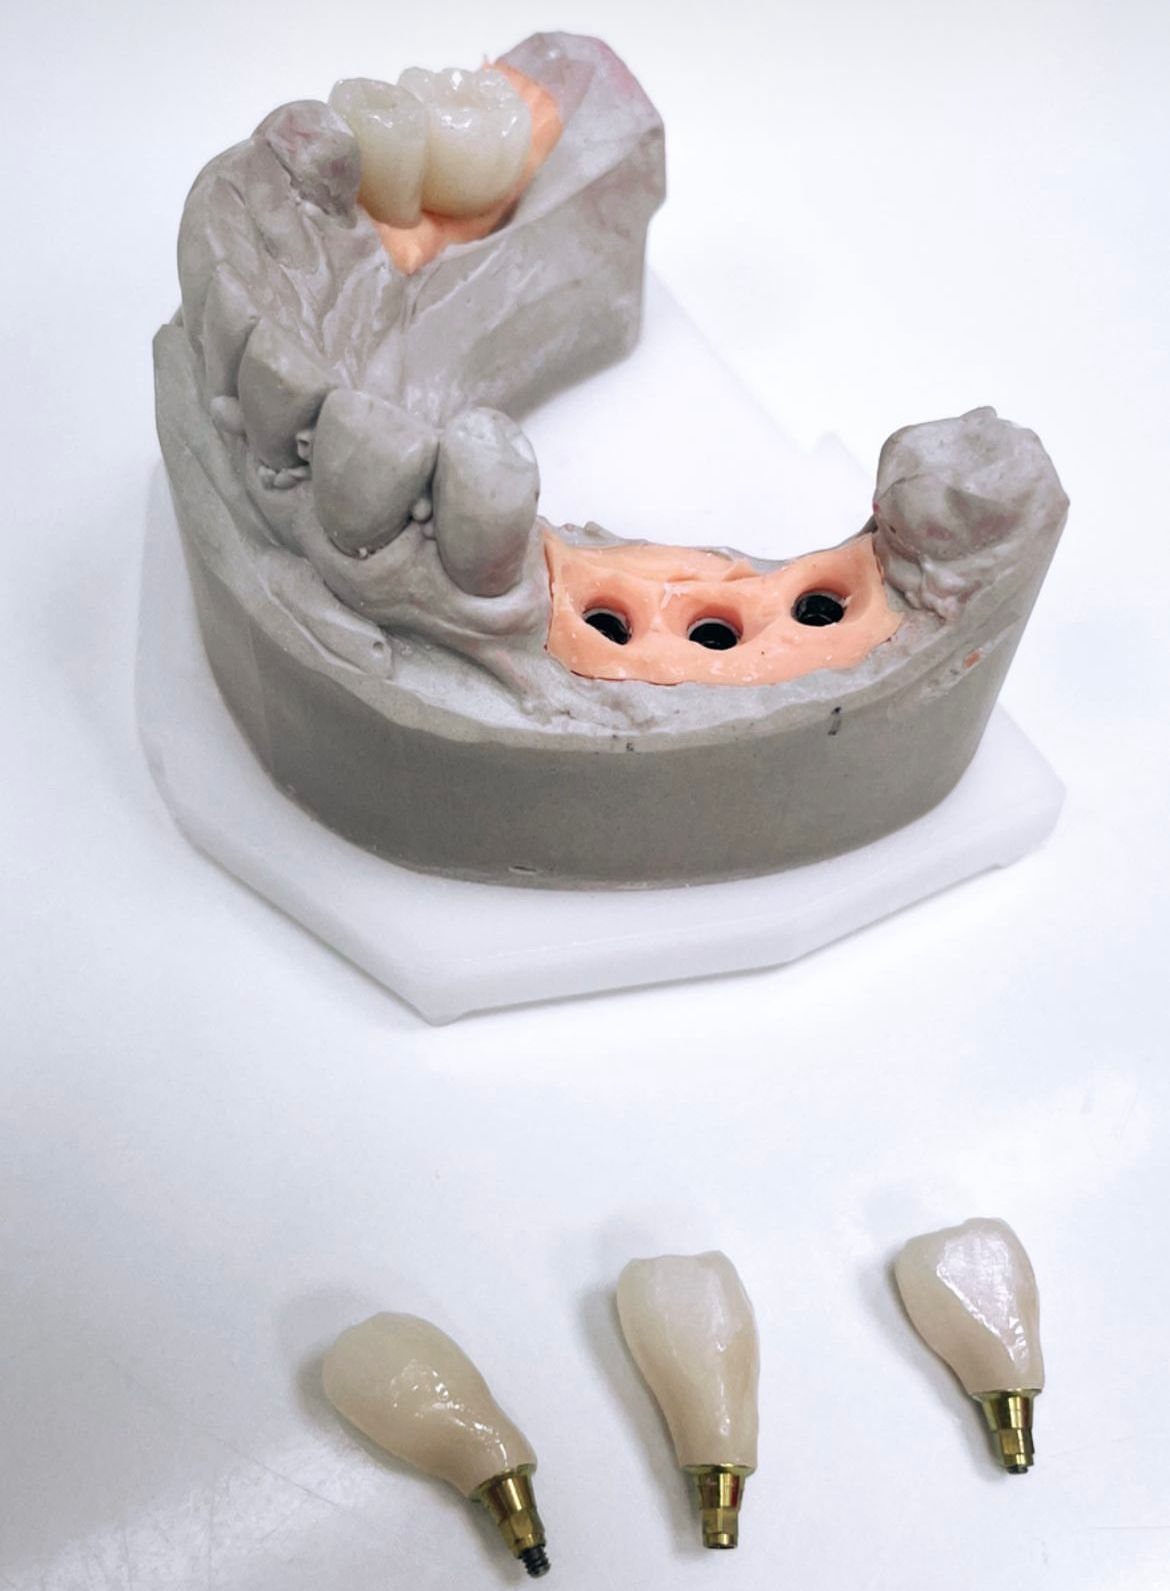

- protetyka (korony ceramiczne (cerkon, E-max), licówki, mosty, protezy ruchome, korony na teleskopach, inlay, onlay, overlay, endkorony);

- implantologia,